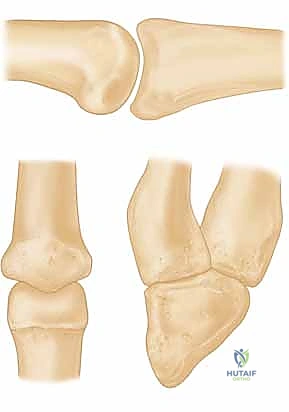

* FIG 1 • A. Unstable PIP fracture-dislocation. The upward pull of the central tendon insertion and the distal superficialis insertion pull and push the middle phalanx up and over the proximal phalangeal head. The only forces preventing dorsal subluxation are the middle phalanx palmar lip and the palmar plate, both of which are lost in an unstable PIP palmar lip fracture.

* FIG 1 • B. PIP instability after a fracture. A direct relation exists between the amount of middle phalanx palmar lip destroyed by the fracture and the resultant PIP joint stability. Articular damage in excess of 50% of the joint surface always renders the joint unstable, whereas fractures involving less than 30% usually are stable. Tenuous fractures (ie, those with articular damage of 30% to 50% of the joint surface), must be assessed with lateral radiographs. If the joint will not stay reduced with less than 30 degrees of flexion, it must be classified as “unstable.”